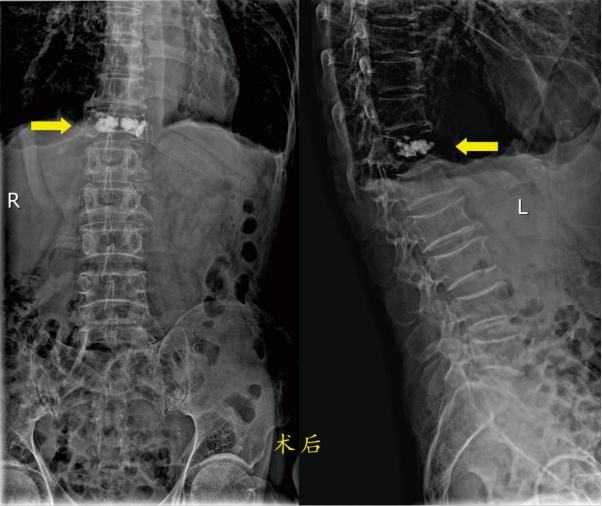

患者1: 高爷爷,男,89岁,因“摔伤致腰背部疼痛活动障碍2天”以“胸椎骨折”2024年6月1日收入骨科住院。入院诊断:1.胸椎骨折(T12),2.腰椎间盘突出,3.慢性阻塞性肺病,4.支气管哮喘,5.肺气肿,6.胸膜肥厚,7.肾结石(双侧),8.单纯性肾囊肿(左侧)。

因高爷爷患有严重的肺部疾病,在不吸氧的情况下血氧饱和度只能维持在80-90%之间,所以手术的风险很大。

胸腰椎骨折的病人,术前需绝对卧床休息,长时间卧床的病人有坠积性肺炎的并发症风险,年龄越大风险越高。骨科医师向患者及家属讲解病情和治疗方法(微创手术或保守治疗即卧床休息)后,经过骨科团队讨论研究,决定为两位患者同样实施微创手术治疗:经皮穿刺椎体成形术。经过术前制定全面的手术方案,在手术室的全力配合下均顺利完成了手术。

高爷爷在下手术台时,就高兴的说:“这手术做的可真好,现在腰背就不痛了!”术后第二天就能下床行走,很快就出院了。